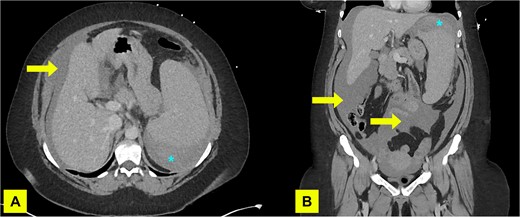

Imaging showed a subphrenic haematoma measuring 15 × 12 cm within the left upper quadrant and moderate volume haemoperitoneum. No active haemorrhage was detected. There were three hypodense splenic lesions of unknown aetiology (vascular, haematologic, or metastatic) and mild splenomegaly (Fig. 1). A diagnosis of atraumatic splenic rupture was made.

A contrast enhanced CT of abdomen and pelvis (portal venous phase) with axial (A) and coronal (B) views performed on admission demonstrating haemoperitoneum (arrows) and subcapsular spleen haematoma (asterisk).